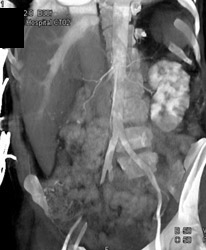

Diagnosis

Sequelae of Ras